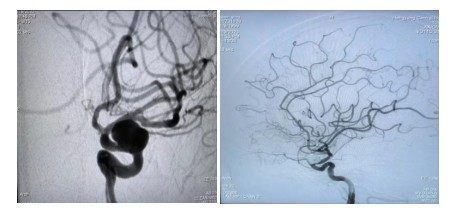

原來64歲的羅奶奶因為發(fā)現(xiàn)頸動脈瘤10余天,來到衡陽市中心醫(yī)院全科醫(yī)學科住院,在完善腦血管造影檢查后,診斷其為左側(cè)頸內(nèi)動脈眼動脈段動脈瘤,瘤體大,并有分葉子瘤,為高危破裂動脈瘤。危急之下,轉(zhuǎn)入神經(jīng)內(nèi)科一病區(qū)準備進行介入手術(shù)治療。

經(jīng)過充分的術(shù)前準備工作,神經(jīng)內(nèi)科中心主任丁菁帶領(lǐng)介入團隊與導管室、麻醉科等多學科共同協(xié)作,順利為羅奶奶實施了血流導向密網(wǎng)支架輔助下顱內(nèi)動脈瘤栓塞術(shù)。手術(shù)過程順利,術(shù)后羅奶奶在麻醉蘇醒后安返病房。在神經(jīng)內(nèi)科一病區(qū)醫(yī)護人員的精心護理下羅奶奶恢復良好,順利出院。

介入治療動脈瘤,是目前國內(nèi)外大中心治療動脈瘤的主要方法。最常見是把動脈瘤腔用微彈簧圈進行填塞,使瘤腔內(nèi)形成血栓達到動脈瘤的致密栓塞、解剖治愈的目的。對于有一些大的動脈瘤瘤頸非常寬,栓塞后仍有很高的復發(fā)率??梢圆捎醚鲗蜓b置,也就是密網(wǎng)支架治療動脈瘤。它是最新的治療方法,我們的羅奶奶就是采用這種治療方法。

密網(wǎng)支架又被稱為血流導向裝置,是一種新型的介入栓塞材料。它在血管內(nèi)跨過動脈瘤釋放支架。由于這個支架的網(wǎng)眼非常小,導絲非常細,會干擾并減少從載瘤動脈進入動脈瘤的血流,使動脈瘤中血流出現(xiàn)阻滯,導致動脈瘤內(nèi)血栓形成,表現(xiàn)為“血流導向”作用;同時它提供血管內(nèi)皮細胞攀爬生長的腳手架,促進內(nèi)皮化修復。它較彈簧圈栓塞操作更簡便,手術(shù)風險降低,更安全。